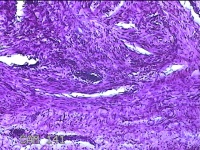

前胸部包块

性别

女

年龄

45岁

临床诊断

皮脂腺囊肿

一般病史

发现前胸部包块3个月余。

标本名称

大体所见

灰白暗红色组织2.2x1x0.8cm一块,表面带梭形皮肤2.2x1.3cm,皮下见包块1.8x1.2x0.8一块,切开包块呈实性,切面灰白粉红色,质软。

图4